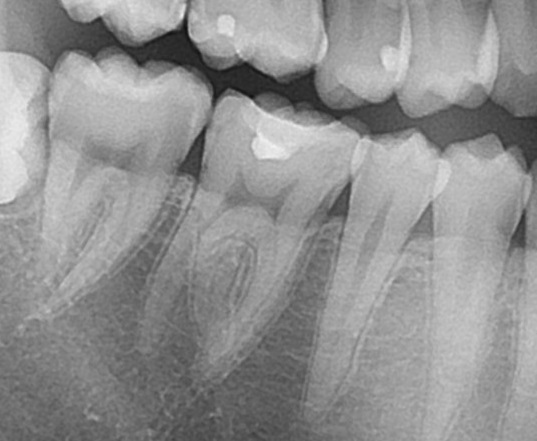

レントゲン写真(エックス線)を見てみると、

右下の歯ですが、奥から2番目、レジンで詰め物がされています。(レントゲンで白く写っています)